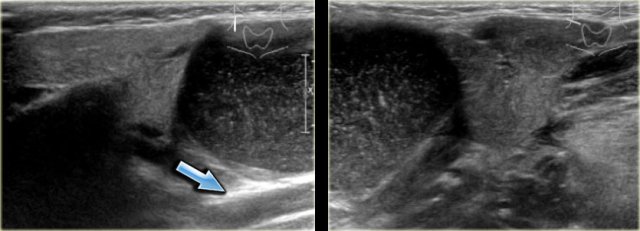

On the left images of a three-year old girl with a slowly enlarging tumor in the midline.

On ultrasound a hypoechoic ovoid smooth bordered lesion is seen at the level of the hyoid bone and slightly right off midline (left image).

During US examination, the lesion moves simultaneously with extrusion of the tongue.

Cystic nature and close relation to the hyoid bone makes thyroglossal duct cyst the most likely diagnosis.

Notice that a normal thyroid gland is present (right image).